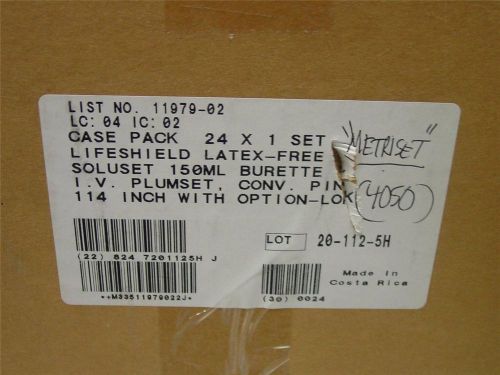

1 case qty 24 I.V. Set 11979-02 abbott Plum omni-flow pumps